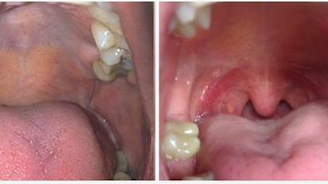

NightLase es fácil de usar para cualquier médico o dentista y tiene un alto índice de éxito a la hora de producir un cambio positivo en los patrones de sueño. Las investigaciones han demostrado que NightLase reduce y atenúa los ronquidos y permite reducir los efectos de la apnea del sueño de forma eficaz y no invasiva.

El tratamiento completo de NightLase consiste en tres sesiones individuals durante un período de semanas. Se ha demostrado que los resultados finales del tratamiento duran hasta un año y la terapia puede repetirse.